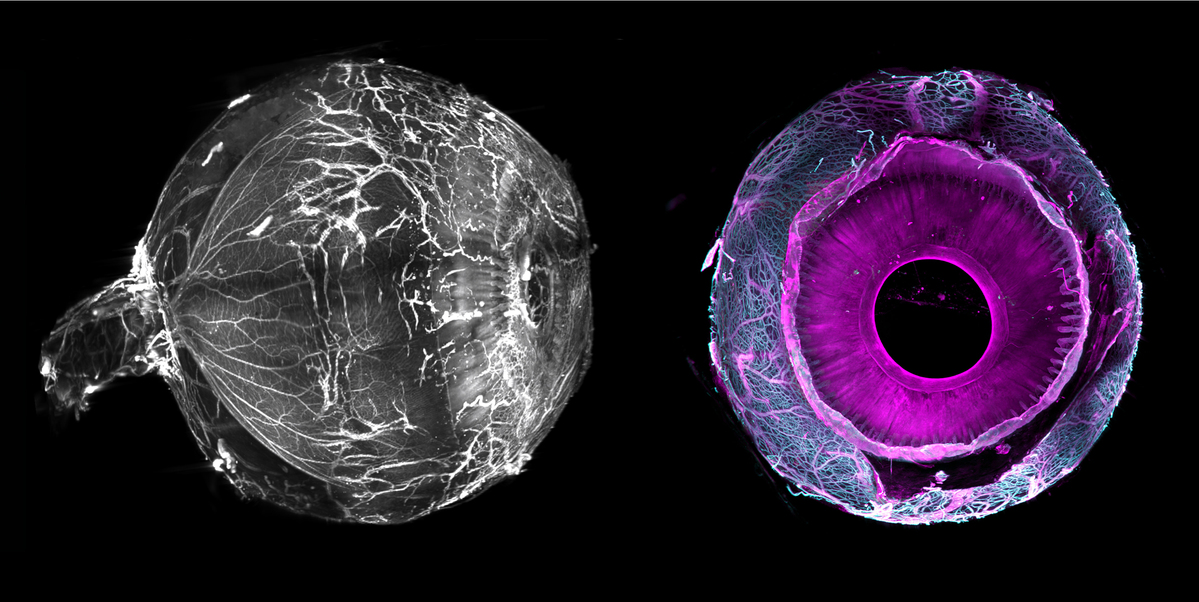

#Innovation : C’est la 1ère fois que vous verrez un œil humain sous cet angle ! 👀Immersion dans la rétine humaine grâce à une équipe @Quinze_Vingts & @Wysscenter qui a imagé par transparisation un œil humain entier pour la première fois au monde ➡ 15-20.fr/actualite/tran…

#Innovation Une première mondiale, des yeux humains entiers imagés par transparisation et microscopie : de nouvelles perspectives pour la recherche ophtalmologique. 👀 Étude la plus détaillée à ce jour des tissus oculaires de l’œil humain. 👏 @CommsBio ➡️15-20.fr/actualite/tran…